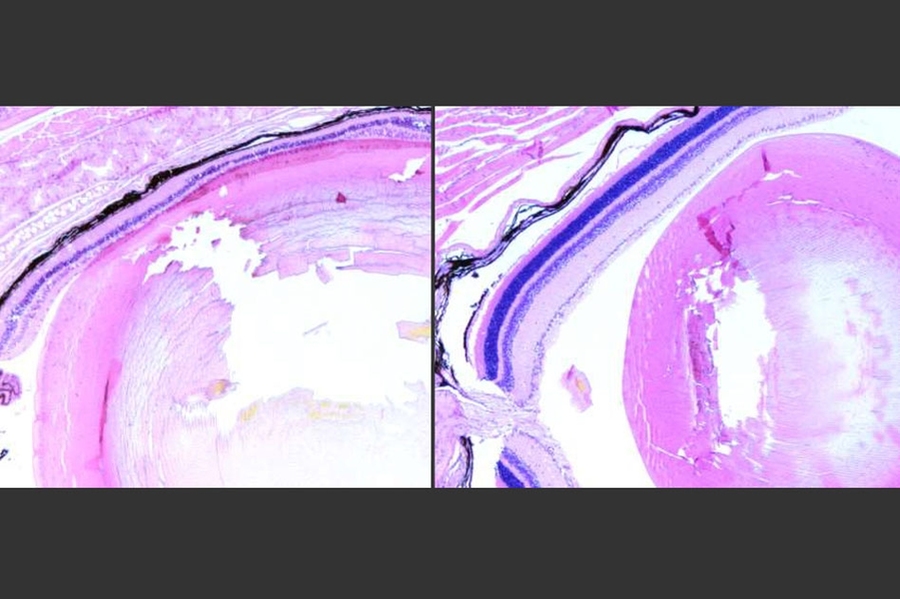

At left, photoreceptor cells of the retina have undergone severe damage after treatment with an alkylating agent. This damage is exacerbated by the DNA repair enzyme Aag. At right, photoreceptor cells lacking Aag appear normal following treatment with the alkylating agent.

Caption: At left, photoreceptor cells of the retina have undergone severe damage after treatment with an alkylating agent. This damage is exacerbated by the DNA repair enzyme Aag. At right, photoreceptor cells lacking Aag appear normal following treatment with the alkylating agent.